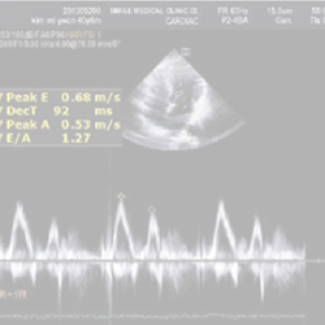

고해상도 첨단 영상장비 구축으로

높은 정밀도의 검진

3.0T MRI / 128CH MDCT / 고해상도 초음파 장비 / 디지털 X-ray / 올림푸스사의 290 고화질 내시경 등 검진의 정밀도를 높입니다.